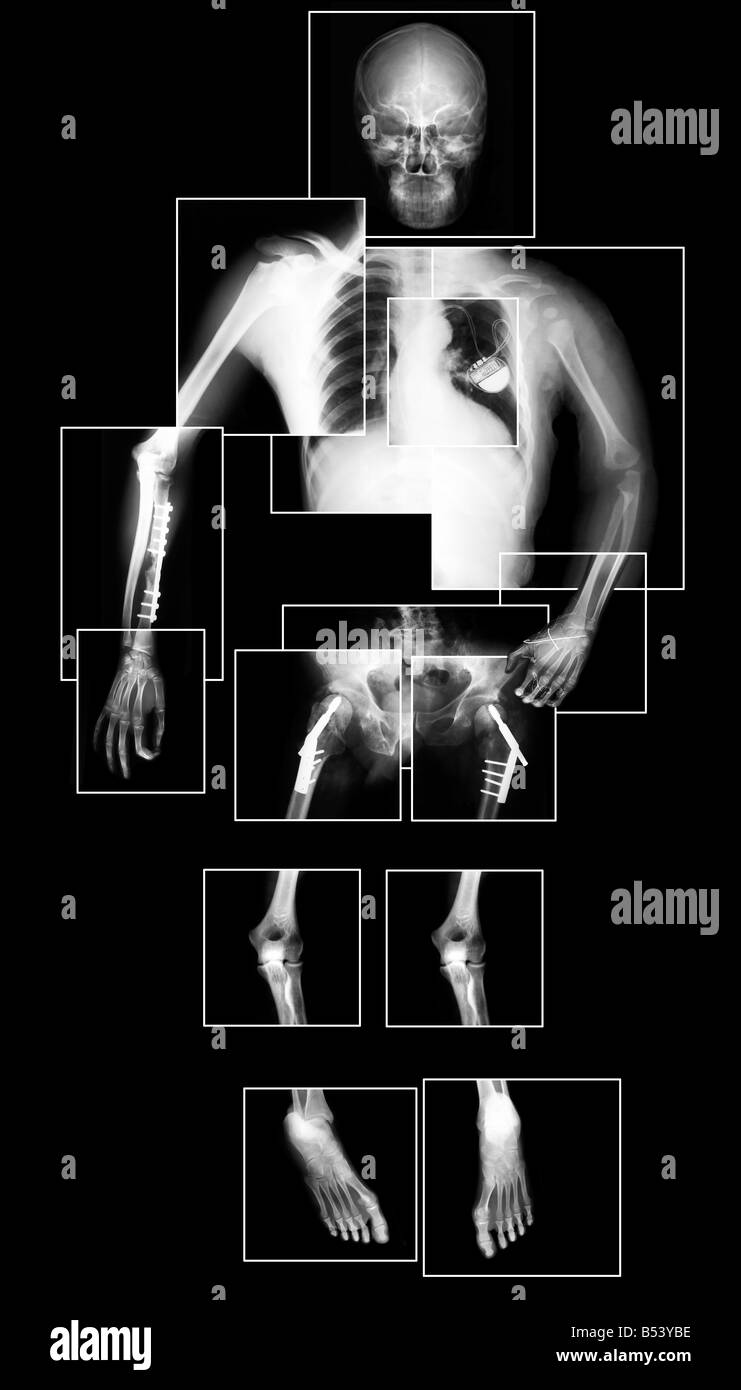

Colección De Alta Calidad De Imagen De Rayos X Muestran Muchas Partes

www.deperu.com

www.deperu.com